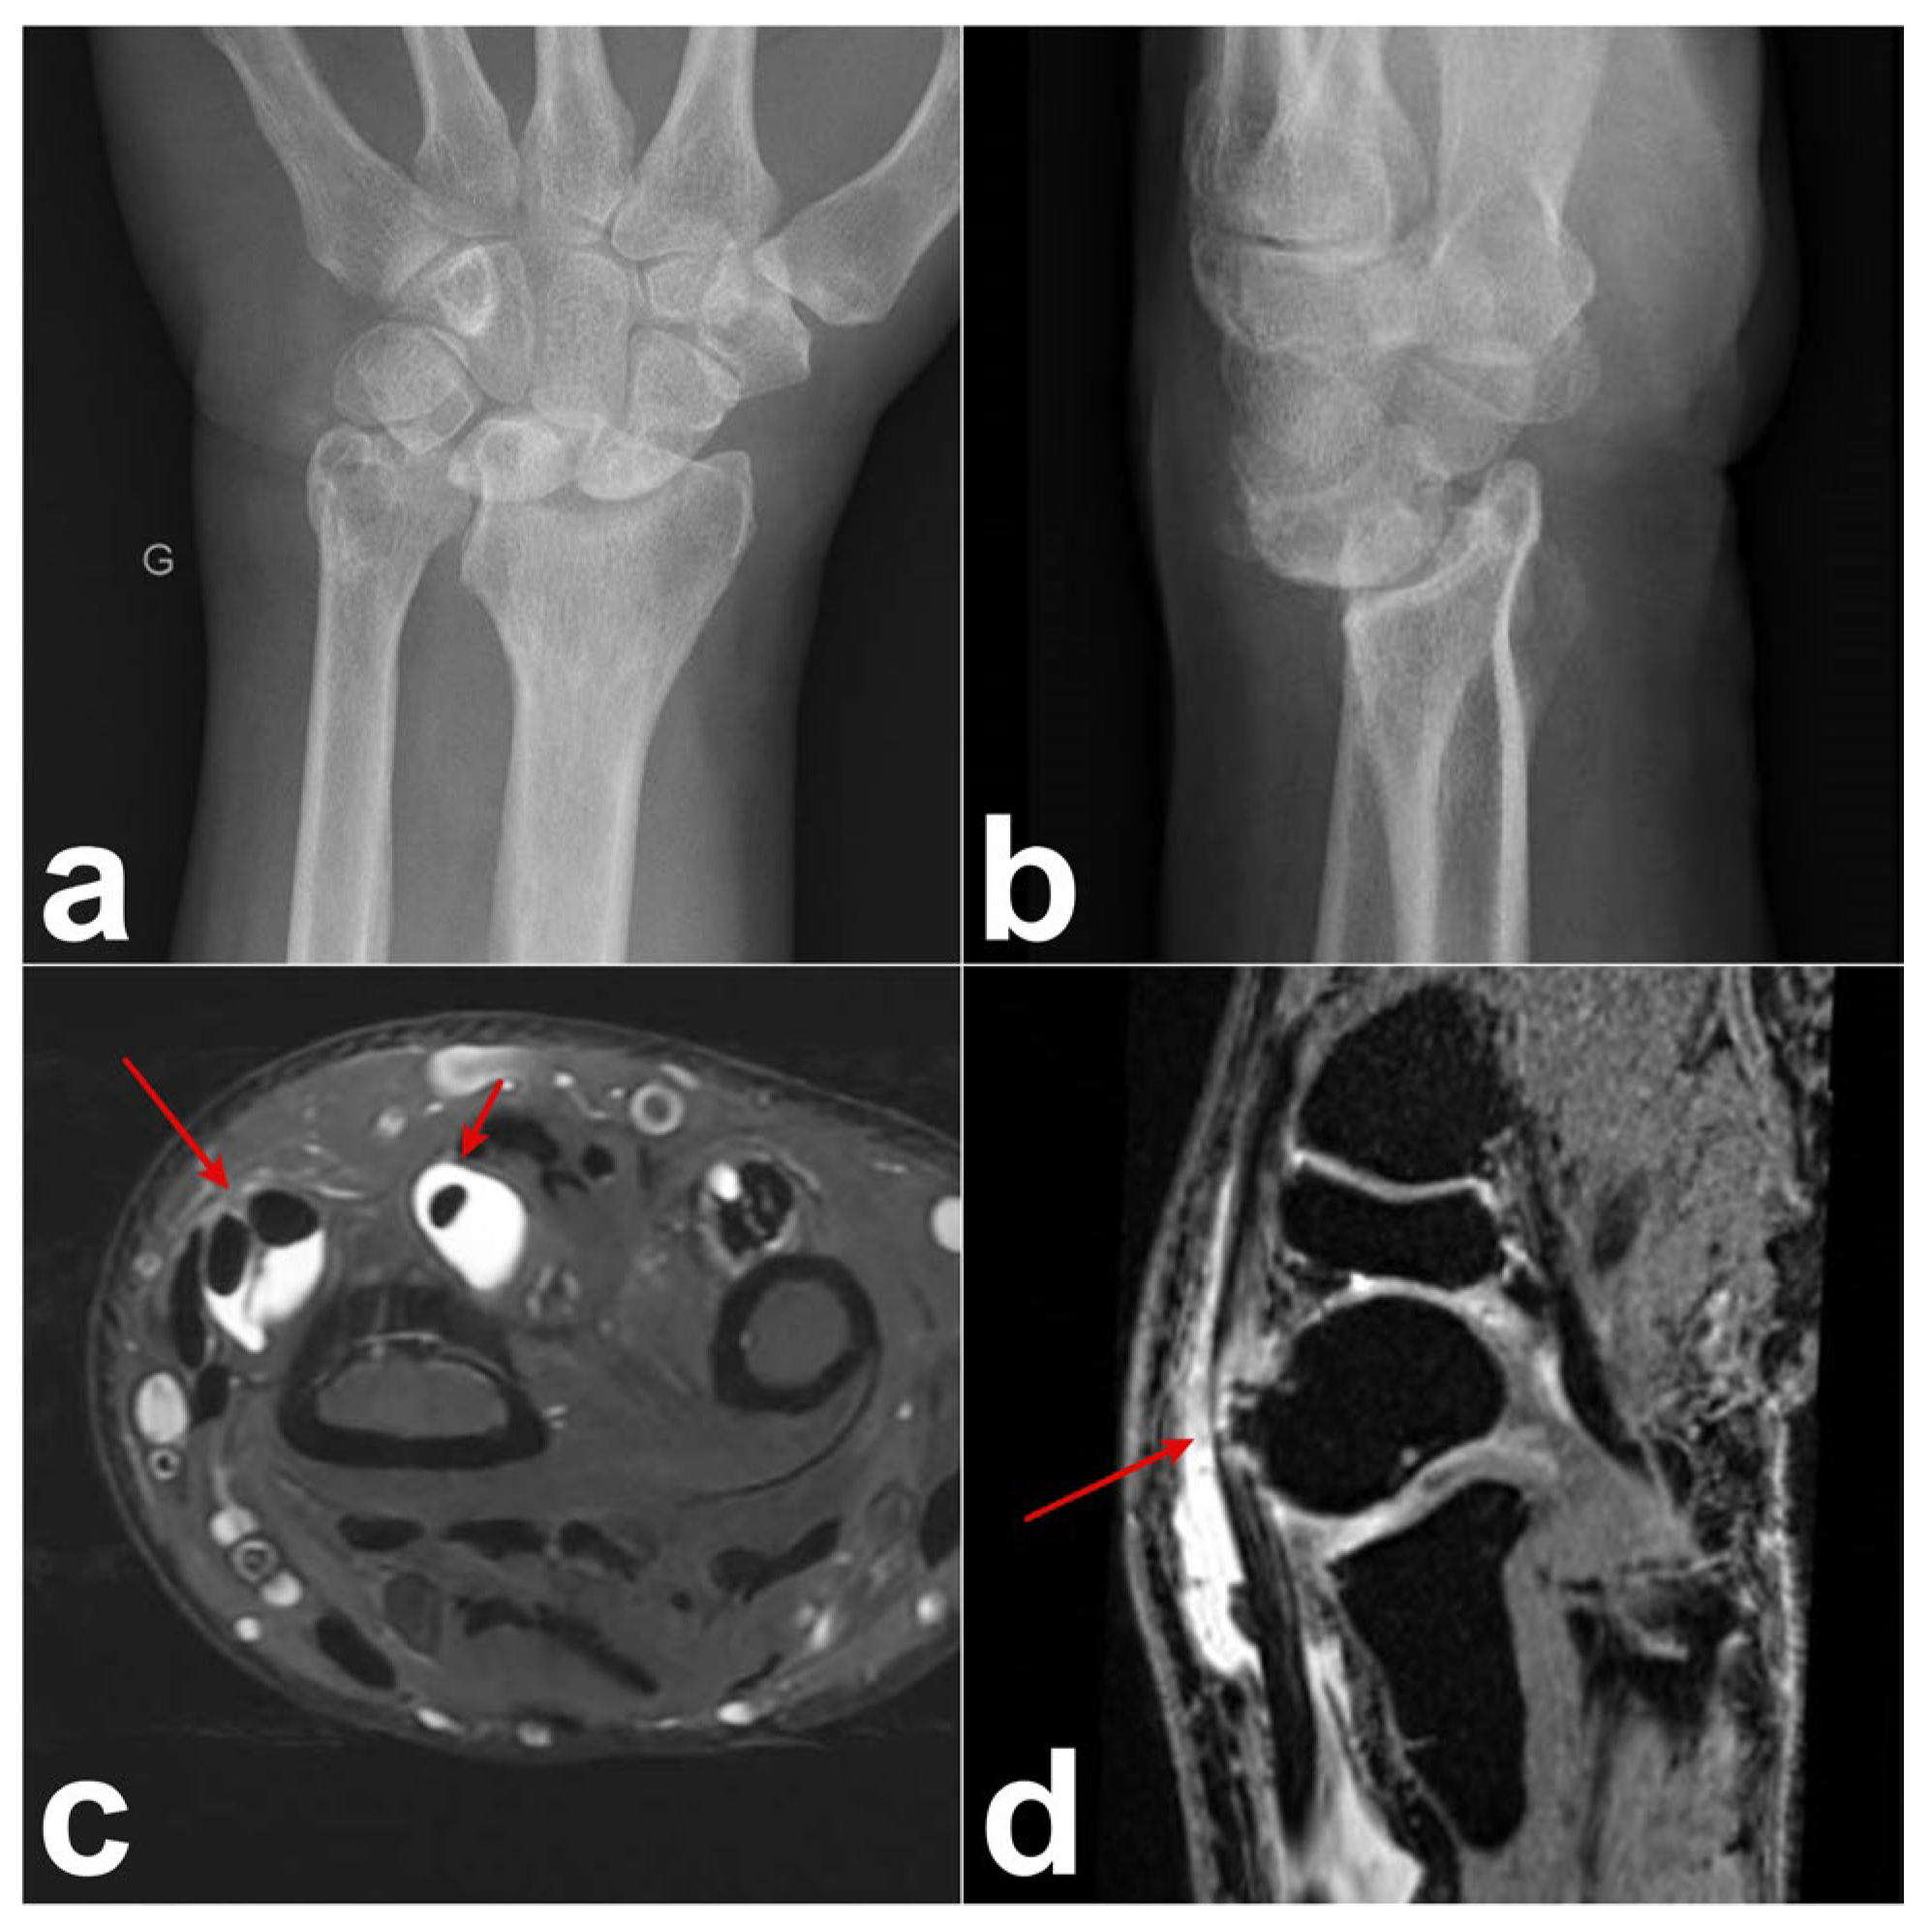

A 60-year-old male, a right-handed manual worker, visited our clinic with intense pain on the dorsal side of his left wrist after lifting heavy objects. Swelling of the dorsoradial aspect of the wrist and painful limited flexion and extension of the wrist were observed. Ultrasound revealed that the swelling was due to the presence of DIT. Radiographs and arthro-MRI highlighted the malunion of the distal radius following a prior fracture treated conservatively. This condition was associated with the dorsal subluxation of the wrist and radioulnar, radiocarpal, and midcarpal osteoarthritis (Figure 2). The proximal scaphoid exhibited structural changes and appeared aggressive toward the ECRB on MRI (Figure 2). Owing to the underlying bone issue, which could not be resolved with conservative treatment, we opted for a surgical procedure. A longitudinal dorsal incision was made and the extensor retinaculum was incised over the third compartment. The EPL was intact, and a communicating foramen was observed between the tendon sheaths of the ECRB and EPL (Figure 3). We observed a perforation at the level of the dorsal wrist capsule, creating direct contact between the proximal pole of the scaphoid and the deep surface of the ECRB (Figure 3). The deep aspect of the ECRB was severely damaged (Figure 3). Proximal row carpectomy, radio-capitate and radio-hamate arthrodesis using CCS screws and the partial denervation of the wrist by resecting the terminal branch of the posterior interosseous nerve were performed. Teno-synovectomy of the ECRB, ECRL, and EPL was conducted, and the subcutaneous transposition of the EPL was performed. Two months after surgery, arthrodesis was fused, the DIT disappeared, and the ultrasound findings normalized.

Figure 2. Case 1. (a,b) Preoperative radiograph showing malunion of the distal radius with dorsal subluxation of the wrist as well as radiocarpal and midcarpal arthritis. (c) Wrist MRI with axial T2-weighted fat-saturated gradient-echo sequence. DIT: Tenosynovitis of the EPL, ECRB, and ECRL (red arrows). (d) Wrist MR arthrogram (T1-weighted VIBE (Volumetric Interpolated Breath hold examination [VIBE) sequence with coronal orientation, isotropic resolution, and water excitation): dorsal subluxation of the scaphoid with signs of remodeling and its abrasive action on the ECRB tendon (red arrow).